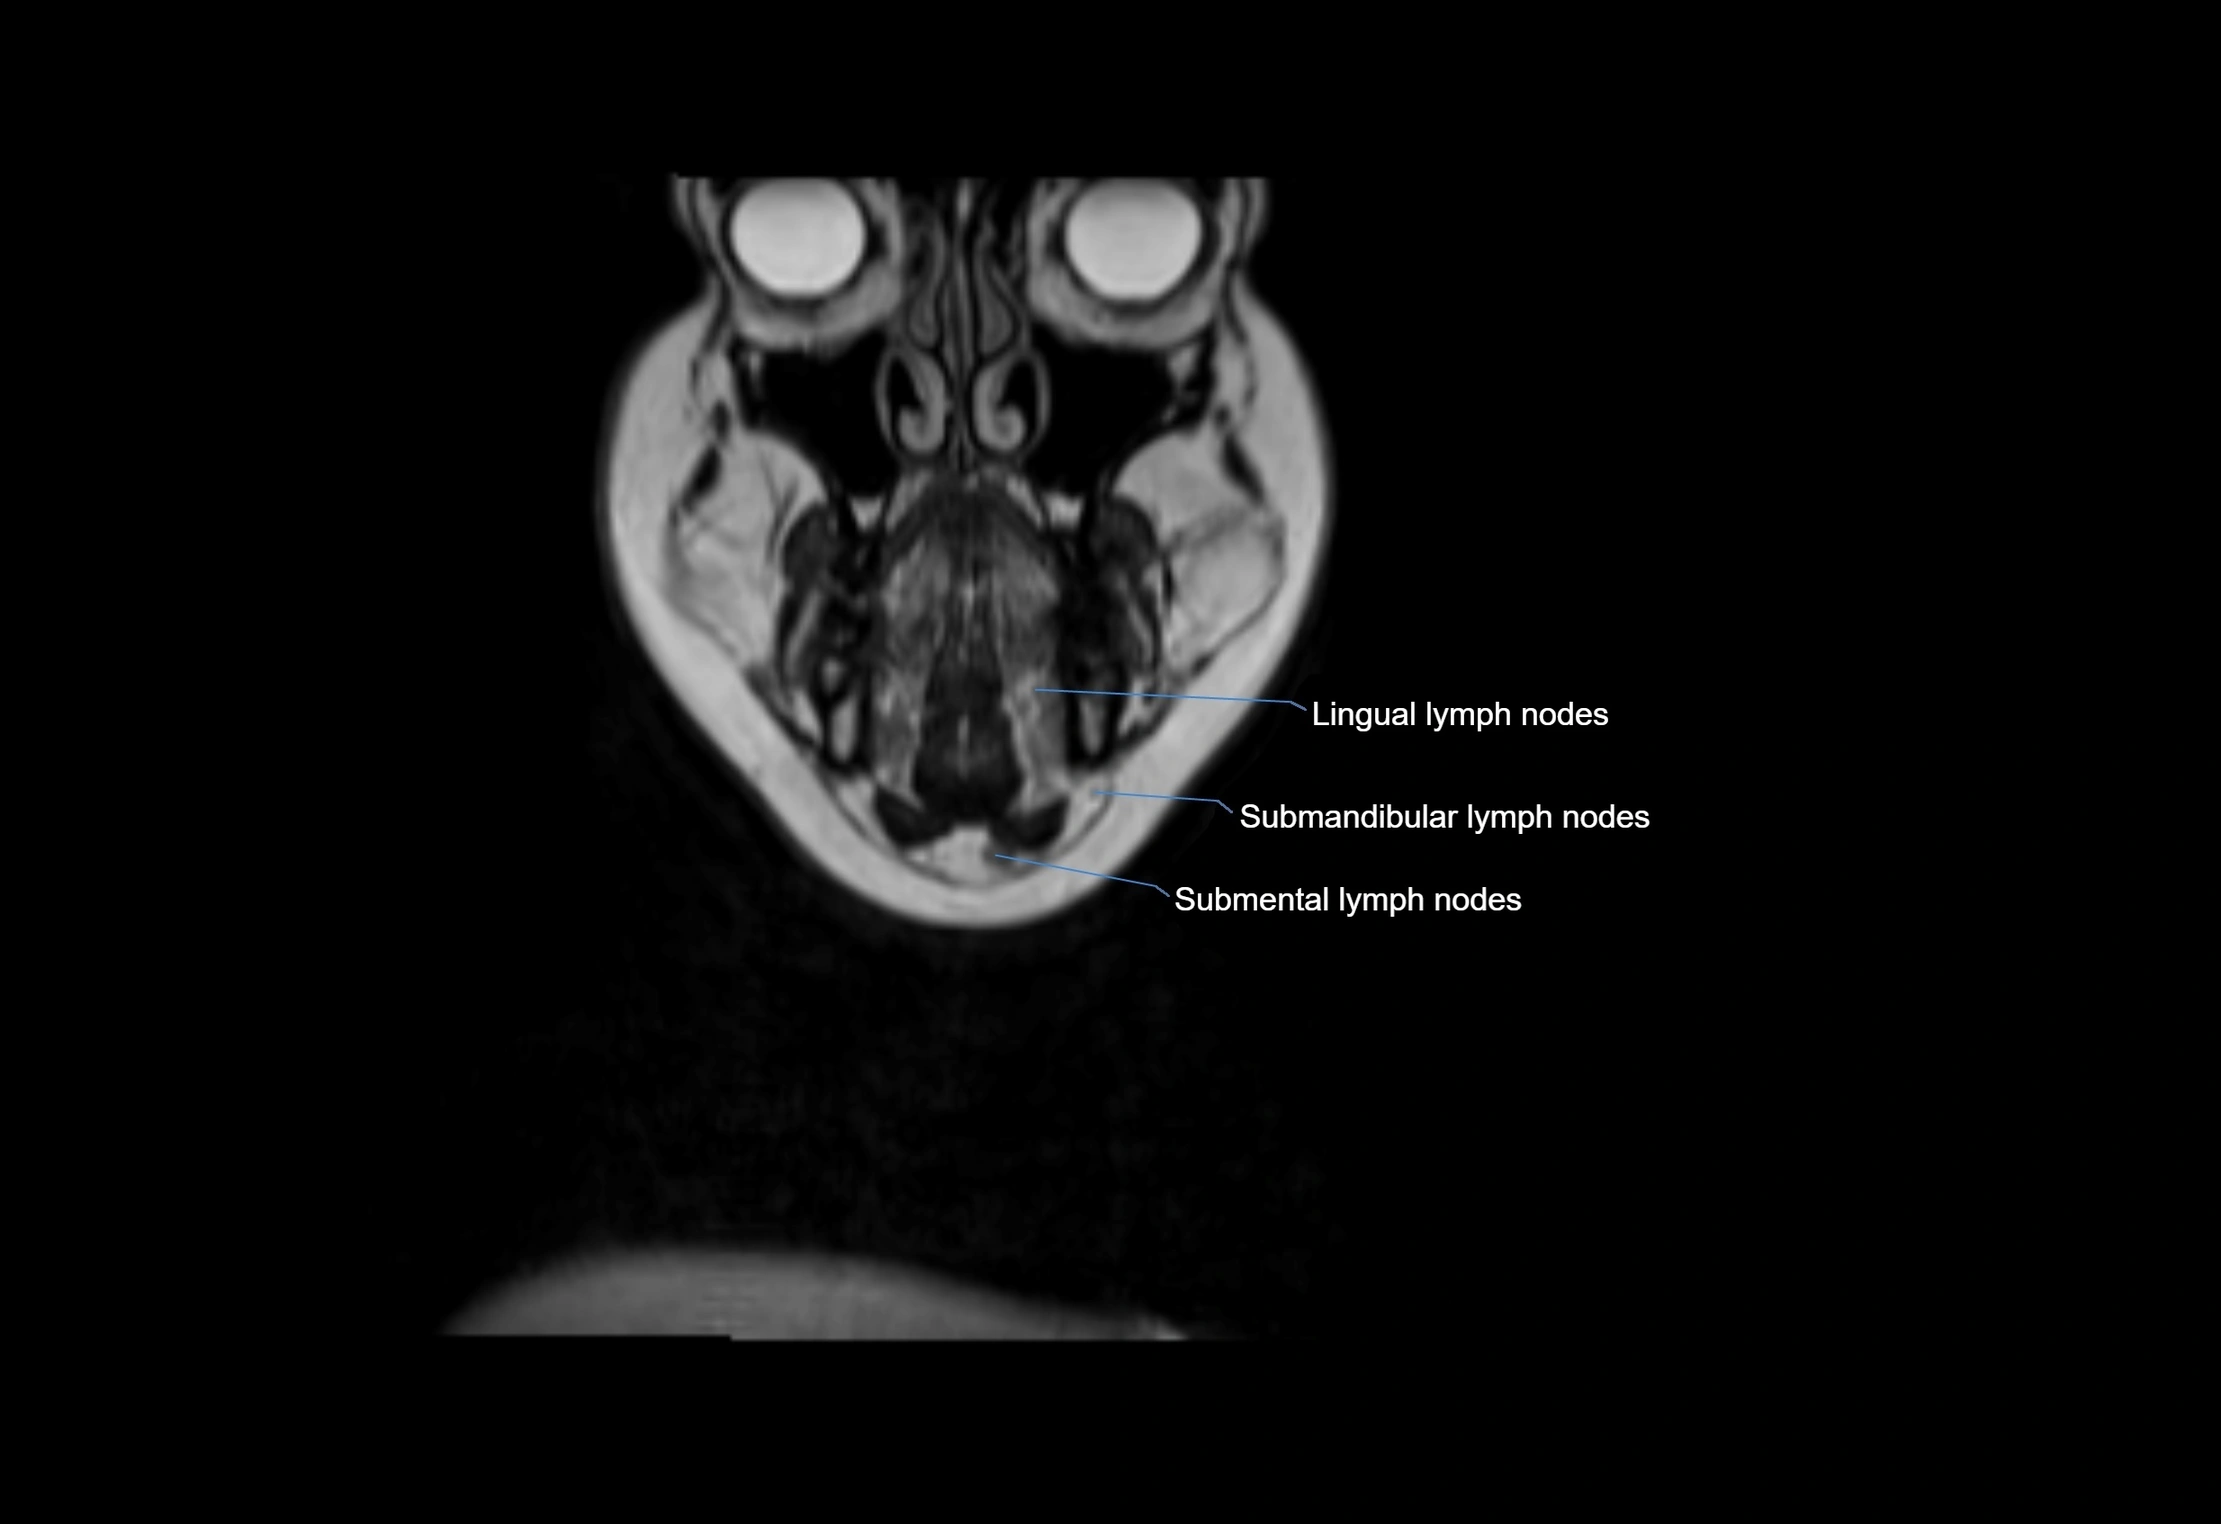

Location

• Found along primary lymph node chains, including preauricular, submandibular, parotid, and occipital regions

• Embedded in subcutaneous fat or superficial fascia, often lateral or posterior to primary nodes

• Variable in number; may occur unilaterally or bilaterally, depending on individual anatomy

MRI Appearance

T1-weighted images:

• Normal accessory nodes appear as small, oval hypointense to intermediate signal structures within subcutaneous fat

• Surrounded by hyperintense fat, enhancing contrast for visualization

• Pathological nodes may appear enlarged or rounded, sometimes with cortical thickening

T2-weighted images:

• Nodes show intermediate signal, with surrounding fat bright

• Useful for detecting edema, inflammation, or infiltration

• Fatty hilum may appear slightly hyperintense relative to cortex

MRI images